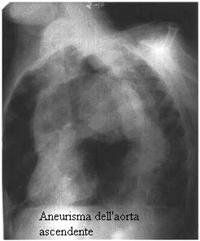

Radiografia del torace

Molte volte è proprio un telecuore a svelare la presenza di un aneurisma dell'aorta toracica. Esso mostra un allargamento dell'ombra mediastinica che, con profilo convesso, sporge verso l'emitorace destro negli aneurismi dell'aorta ascendente e della porzione anteriore dell'arco, e verso quello sinistro negli aneurismi dell'aorta discendente e della porzione posteriore dell'arco.

Il limite dell'indagine radiologica è rappresentato dall'alto numero di falsi positivi per cui la specificità diagnostica è bassa (70-86%).

RX TORACE